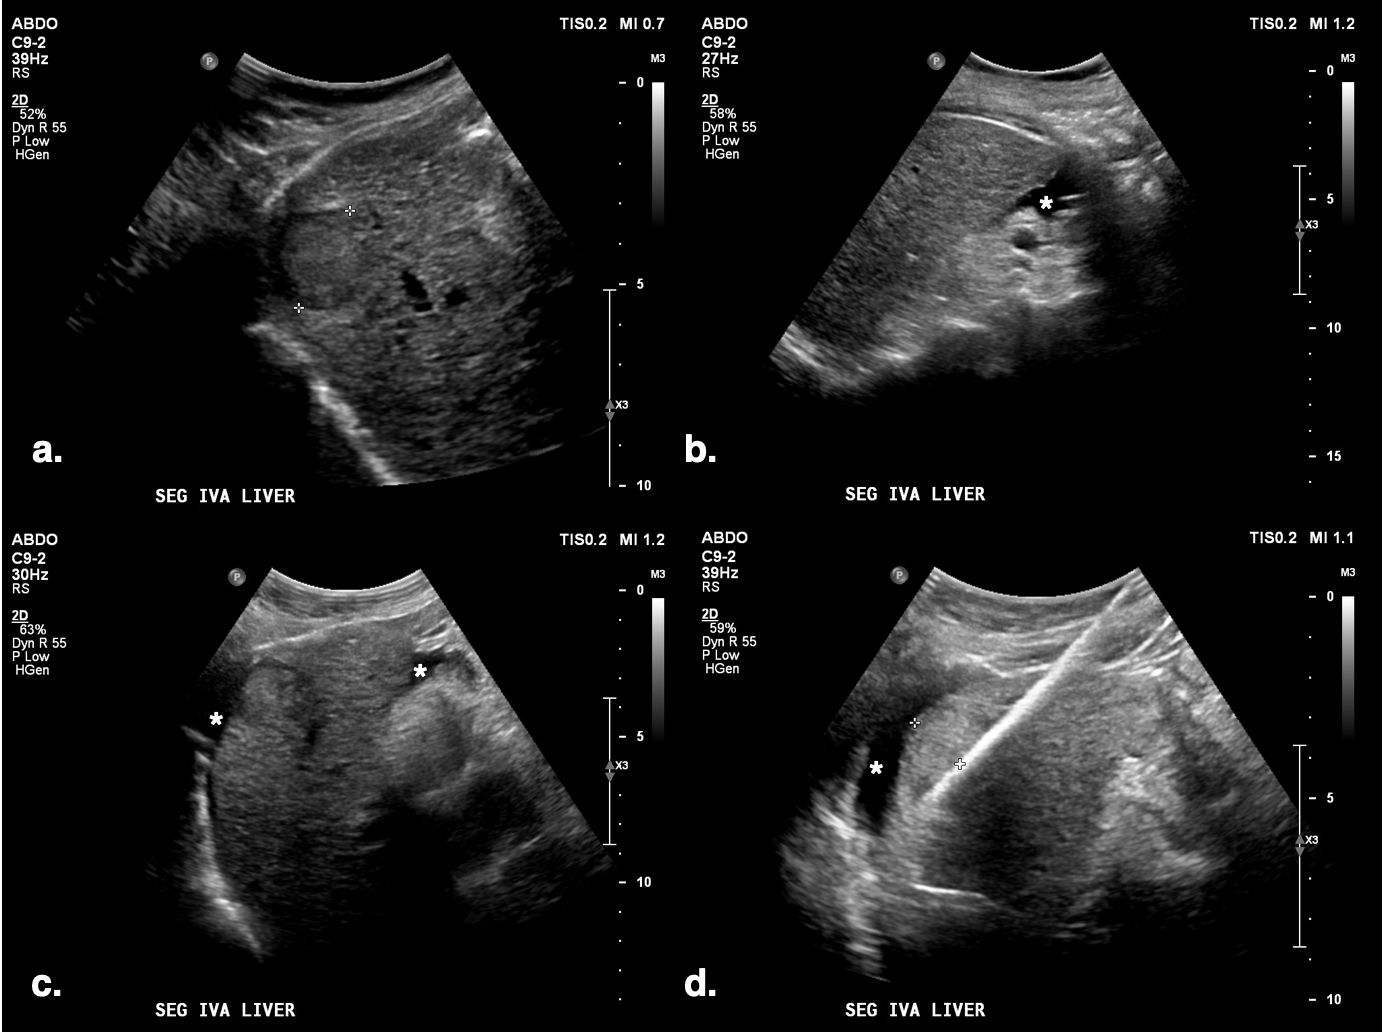

PocketVu features lightweight, multiple scanning modes, AI-powered auto image quality adjustment, compatibility with DICOM 3.0 systems, and long battery life, the company said, adding that PocketVu supports a range of applications, including abdominal, cardiac, musculoskeletal, vascular, and obstetric imaging.